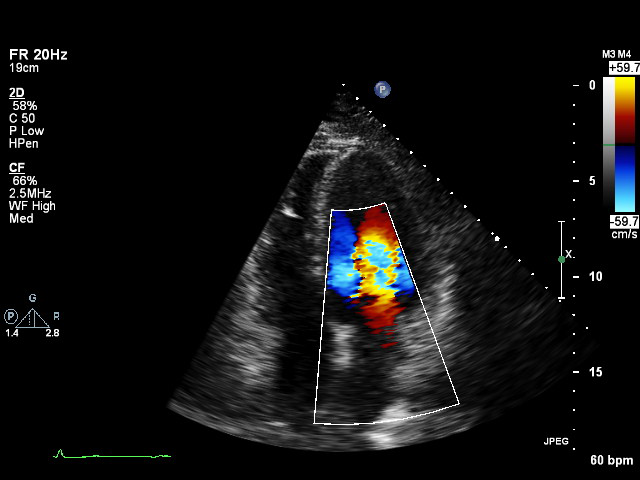

plax-full-la plax-full-la Parasternal long-axis, sector covers whole LA; intended for LA measurements

plax-full-lv plax-full-lv PLAX with imaging sector covering LV but not the whole LA

plax-full-mv plax-full-mv PLAX centered on MV (heavy zoom losing LA/LV parts or MV colour)

plax-full-out plax-full-out Zoomed-out PLAX

plax-full-rv-ao plax-full-rv-ao Focus on RV & aorta or colour Doppler over RV/AV/Aorta

plax-tv plax-tv Parasternal inflow view including tricuspid valve

plax-valves-av plax-valves-av PLAX focused on the aortic valve

plax-valves-mv plax-valves-mv PLAX focused on the mitral valve